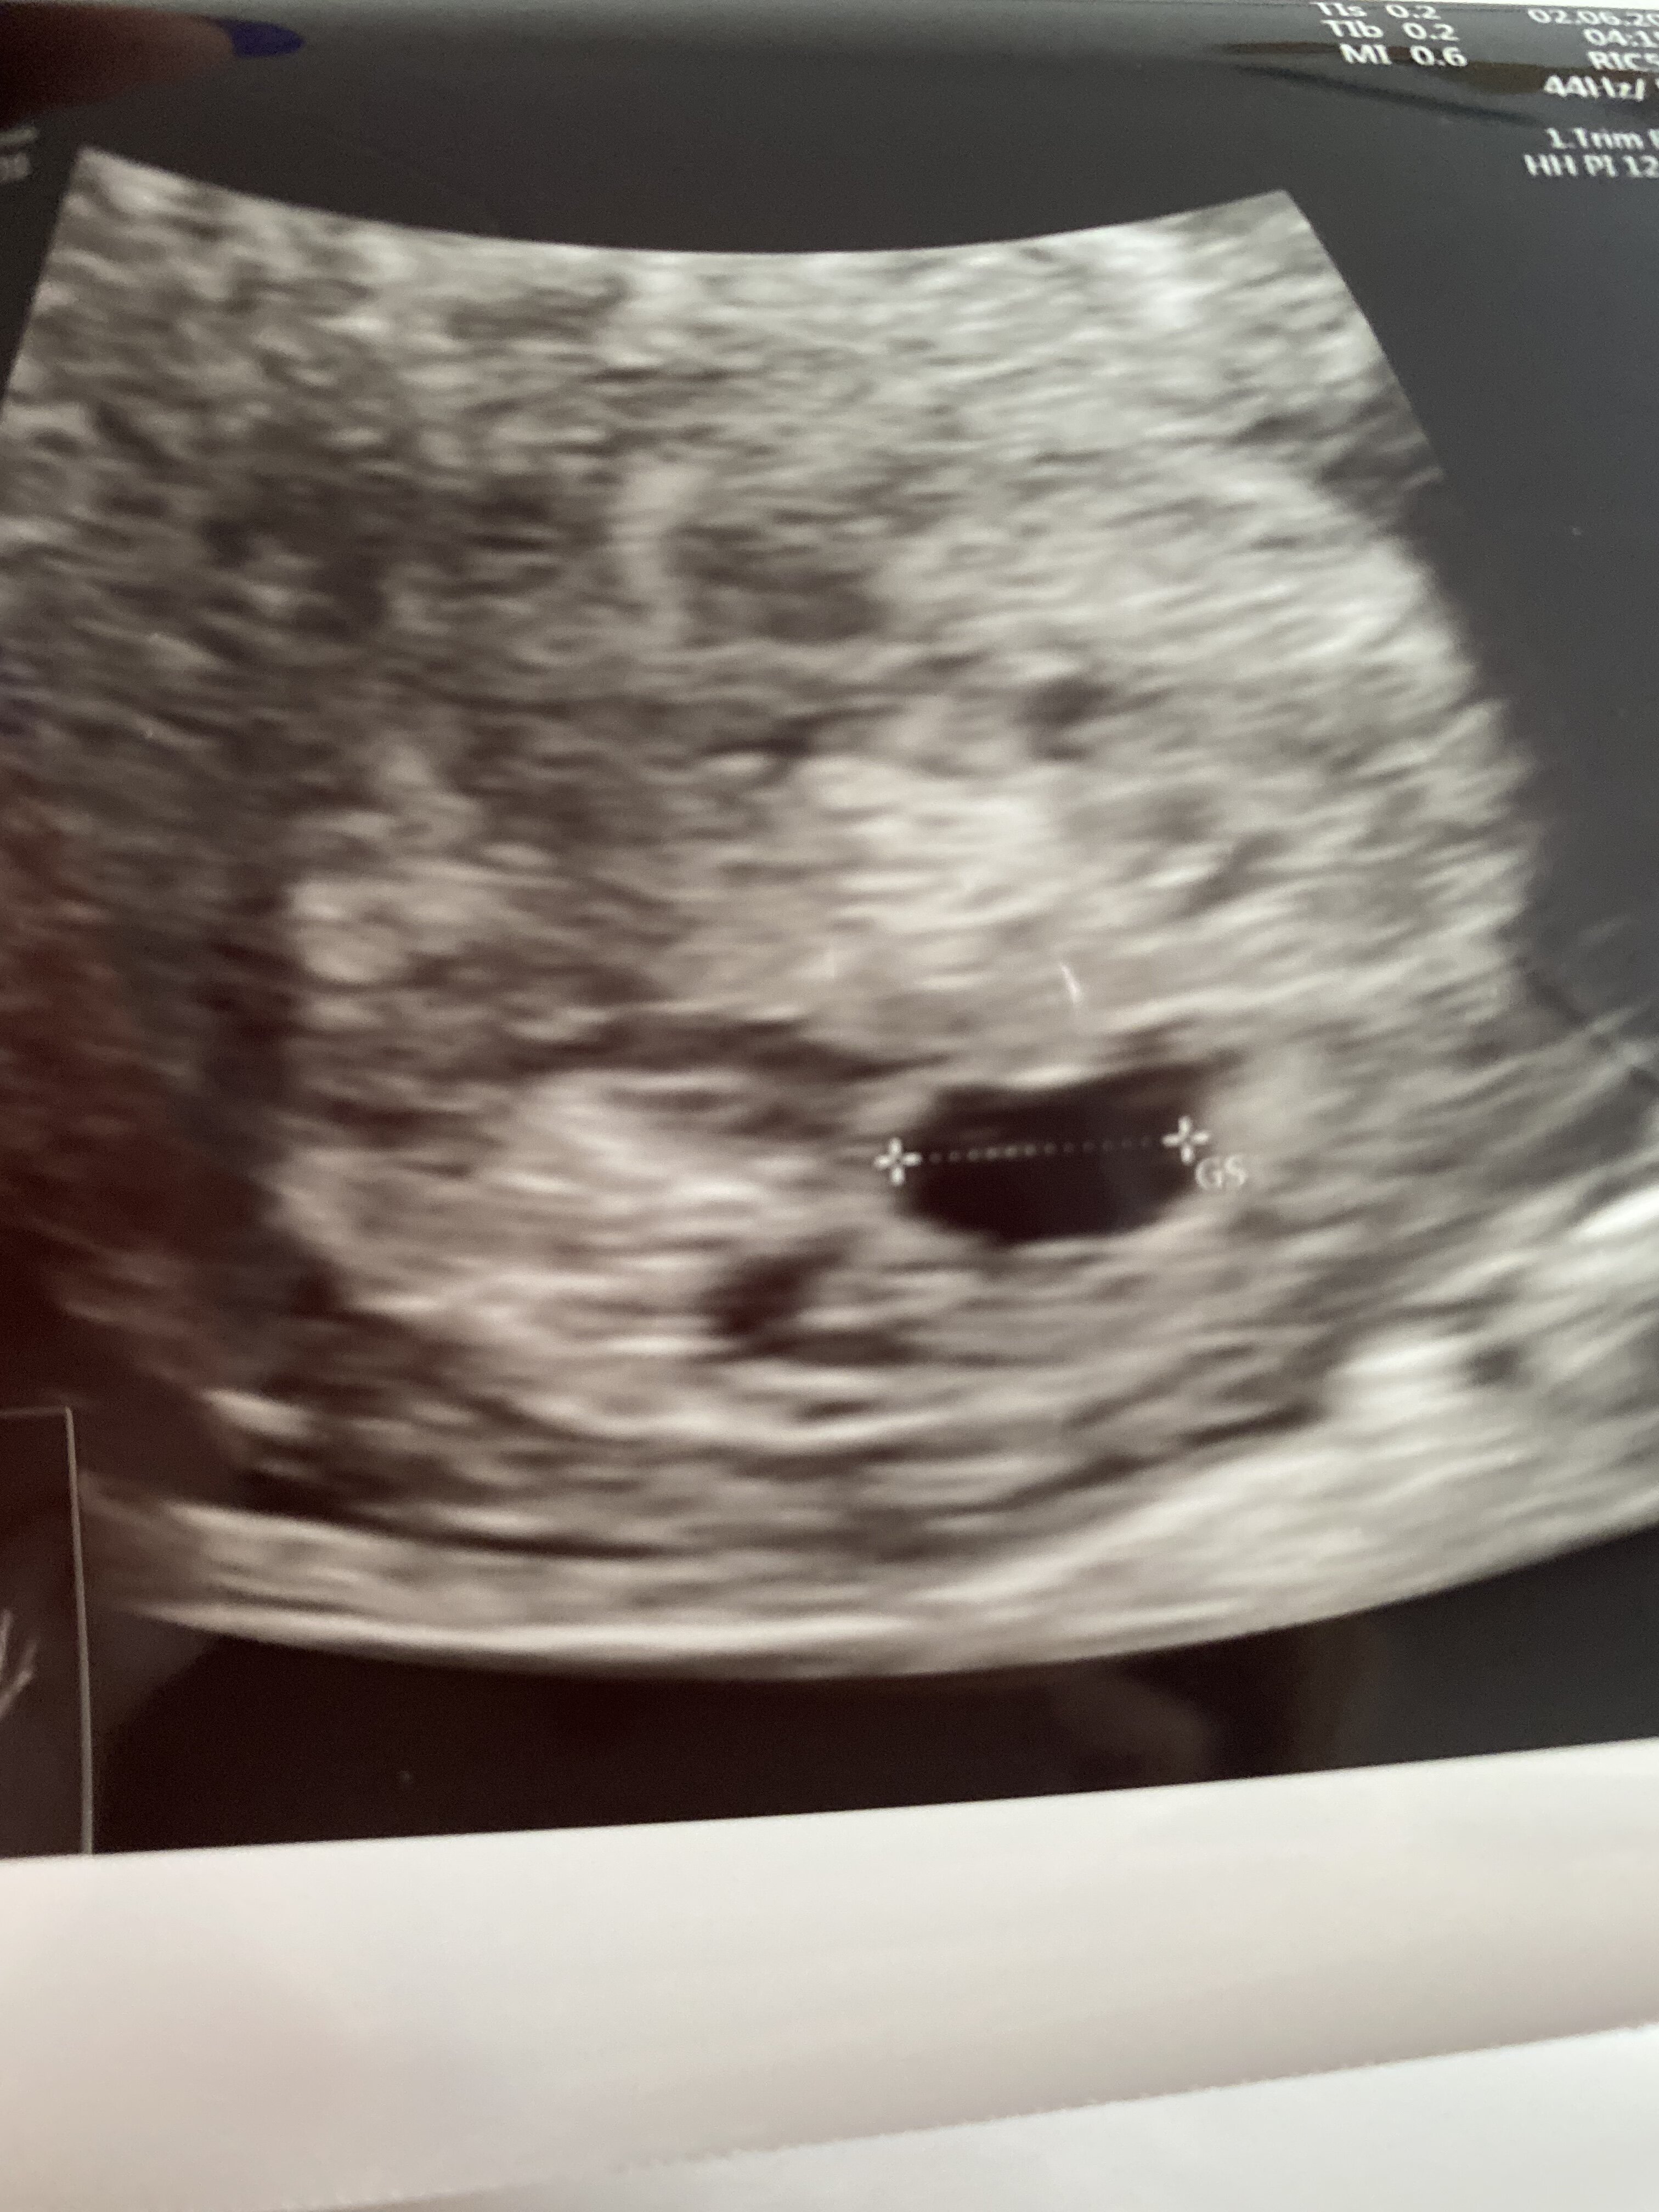

jestem jeszcze baaaaardzo bardzo malutki mam ponad mm , mieszkam sobie w pięknym okrąglutkim 6cio mm. pęcherzyku umiejscowionym w macicy mamusi . Pani dr mówiła ze widac przebłyski pulsowania ale to dopiero początki i aby usłyszeć moje serduszko mamusia jeszcze troszkę poczeka 😍. Biedna mami się wzruszyła i poleciały łezki , łezki szczęścia . Piekne emocje ❤️

jestem jeszcze baaaaardzo bardzo malutki mam ponad mm , mieszkam sobie w pięknym okrąglutkim pęcherzyku umiejscowionym w macicy mamusi . Pani dr mówiła ze widac przebłyski pulsowania ale to dopiero początki i aby usłyszeć moje serduszko mamusia jeszcze troszkę poczeka 😍. Biedna mami się wzruszyła i poleciały łezki , łezki szczęścia . Piekne emocje ❤️

jestem jeszcze baaaaardzo bardzo malutki mam ponad mm , mieszkam sobie w pięknym okrąglutkim 6cio mm. pęcherzyku umiejscowionym w macicy mamusi . Pani dr mówiła ze widac przebłyski pulsowania ale to dopiero początki i aby usłyszeć moje serduszko mamusia jeszcze troszkę poczeka [emoji7]. Biedna mami się wzruszyła i poleciały łezki , łezki szczęścia . Piekne emocje [emoji3590]